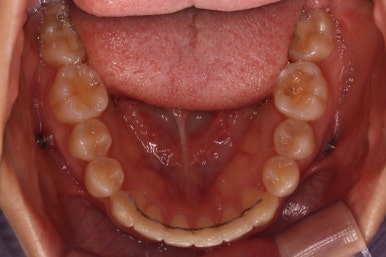

위 사진은 연산동교정치과 처음 내원하셨을 때의 입안 모습입니다. 몇 가지 모습이 관찰됩니다.

치아가 삐뚤삐뚤합니다.

위~아래 앞니가 많이 겹쳐서 아랫니가 많이 모이지 않는 "과개교합" 입니다.

앞니가 앞으로 뻐뜨러져 있습니다.